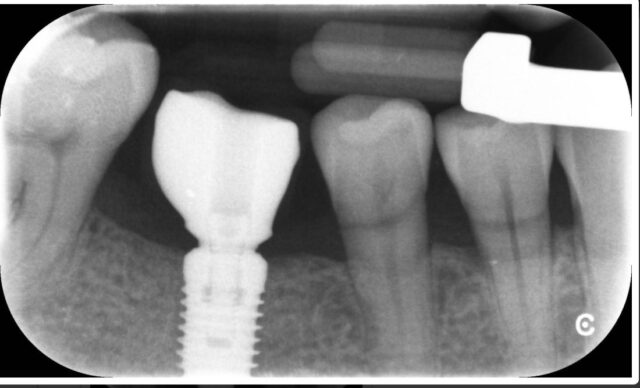

I try-in this implant crown (acrylic crown), is the crown well seated?

Hey @jason im attaching the picture you were trying to show 🙂

I personally don’t use this system. But the seating definitely looks questionable to me. Is this a temporary crown? I think it is worth taking it off checking contacts, and wiggling it to see if you can get a deeper engagement. Confirming with x-rays, of course. I believe that @restoredsmiles uses this system. Can you share your thoughts, Jed?